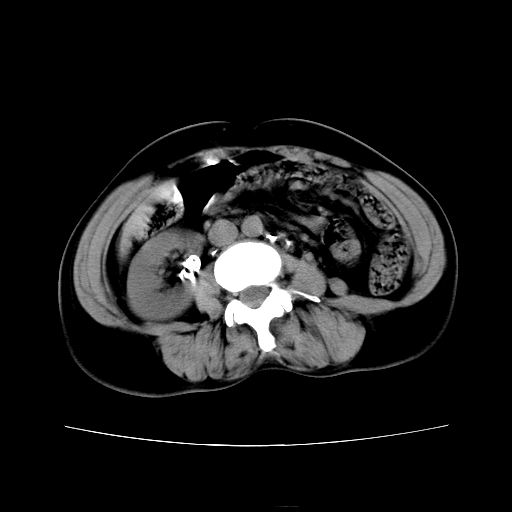

女45y多次(7次)碎石,结果不理想!曾碎石后尿出小碎石,仍腰痛,要求ct,其它不详.本人更倾向于钙化斑!无肾实质破坏,积水等提示集合系统无梗阻.另外腹腔多处钙化.是否结核后改变!谢谢赐教!

考虑双侧肾结石,碎石一般只用于输尿管,膀胱及尿道结石,肾结石特别是无梗阻的肾结石不主张采用碎石的,有可能会搞得收不了场,再者也效果不好,无甚必要,大可以手术

1)双肾结石。2)脾脏钙化灶。3)腹膜后多发淋巴结钙化。

尿路结石与腹部淋巴结钙化共存,建议v尿路造影检查,免得钙化灶冤枉为结石受罚。

考虑双肾结石,肾脏实质无破坏表现,没有结核病史,不考虑肾结核,